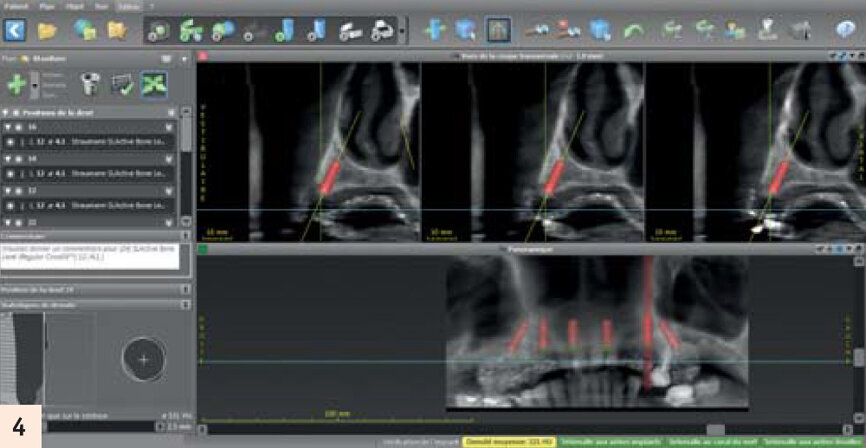

Elle porte un appareil amovible au maxillaire, côtoyant 5 dents naturelles. Elle souhaite une solution fixe (Figs. 1, 2, 3). Après empreintes, mise en articulateur et confection d’un guide radiologique, un examen 3D est réalisé. L’analyse des fichiers DICOM’s transférés sur le logiciel de planification CoDiagnostiX, confirme un faible volume osseux.5Les sinus ont fortement pneumatisé le maxillaire et les parois antérieures sont au niveau des canines.

- Traitement de l’arcade complète : extraction des dents restantes, répartition de 6 implants. Mise en charge immédiate avec un bridge fixe transvissé dans la journée (Fig. 4).

Après concertation et plusieurs rendez-vous de bilan avec notre patiente, la décision finale est la seconde solution. L’objectif est d’utiliser le prémaxillaire pour placer 6 implants sans greffe. Pour gagner en étendue et rétablir une arcade dentaire allant de la 16 à 26, les 2 implants d’extrémité seront inclinés avec une sortie en position de 2e prémolaire. Ainsi, le cantilever sera réduit.L’article de Krekmanov démontre qu’une extension plus grande sur un implant droit a de moins bons résultats qu’une petite extension sur implant incliné.8 D’autres articles prouvent également l’excellent pronostic de ces implants et le niveau osseux équivalent dans le temps par rapport aux implants droits.1

Planification sur le logiciel de planification CodiagnostiX après Cone Beam avec gouttière radio-opaque.

Notre difficulté est d’utiliser le volume osseux au maximun, et de reculer le plus possible les implants distaux. Une telle chirurgie n’est possible que par une planification rigoureuse sur un logiciel, pour avoir une vue d’ensemble, et de voyager millimètre par millimètre dans le maxillaire dans toutes les directions de l’espace.

Ayant moins de volume dans le secteur droit, nous décidons de poser notre implant distal dans la paroi antérieure du sinus. Quelques spires seront dans le sinus mais avec un excellent ancrage. C’est exactement ce même résultat qui est obtenu lorsqu’un implant est placé dans un septum sinusien.6 La corticale vestibulaire des insicives est d’une finesse extrême.